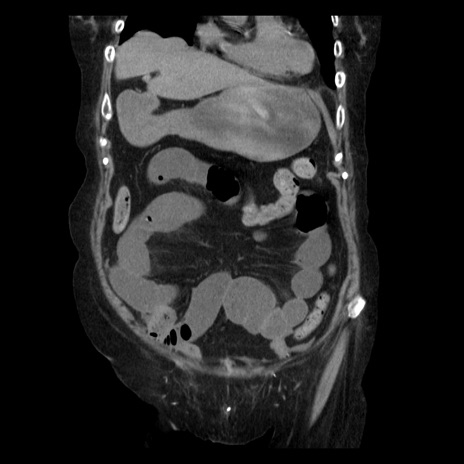

症例14(冠状断像)

【症例】 90歳代女性

【主訴】 腹痛・嘔吐

【現病歴】今朝から左側腹部痛を認めた。 経過観察していたが、嘔吐を認めたため来院。

【既往歴】 子宮癌術後

【身体所見】 意識清明、BP 127/54mmHg、P 98bpm Sp02 95%(RA)、BT 35.8°C、腹部平坦・軟腸ぜん動音聴取良好、右下腹部圧痛(+) 反跳痛なし

【データ】WBC 9800、CRP 0.46